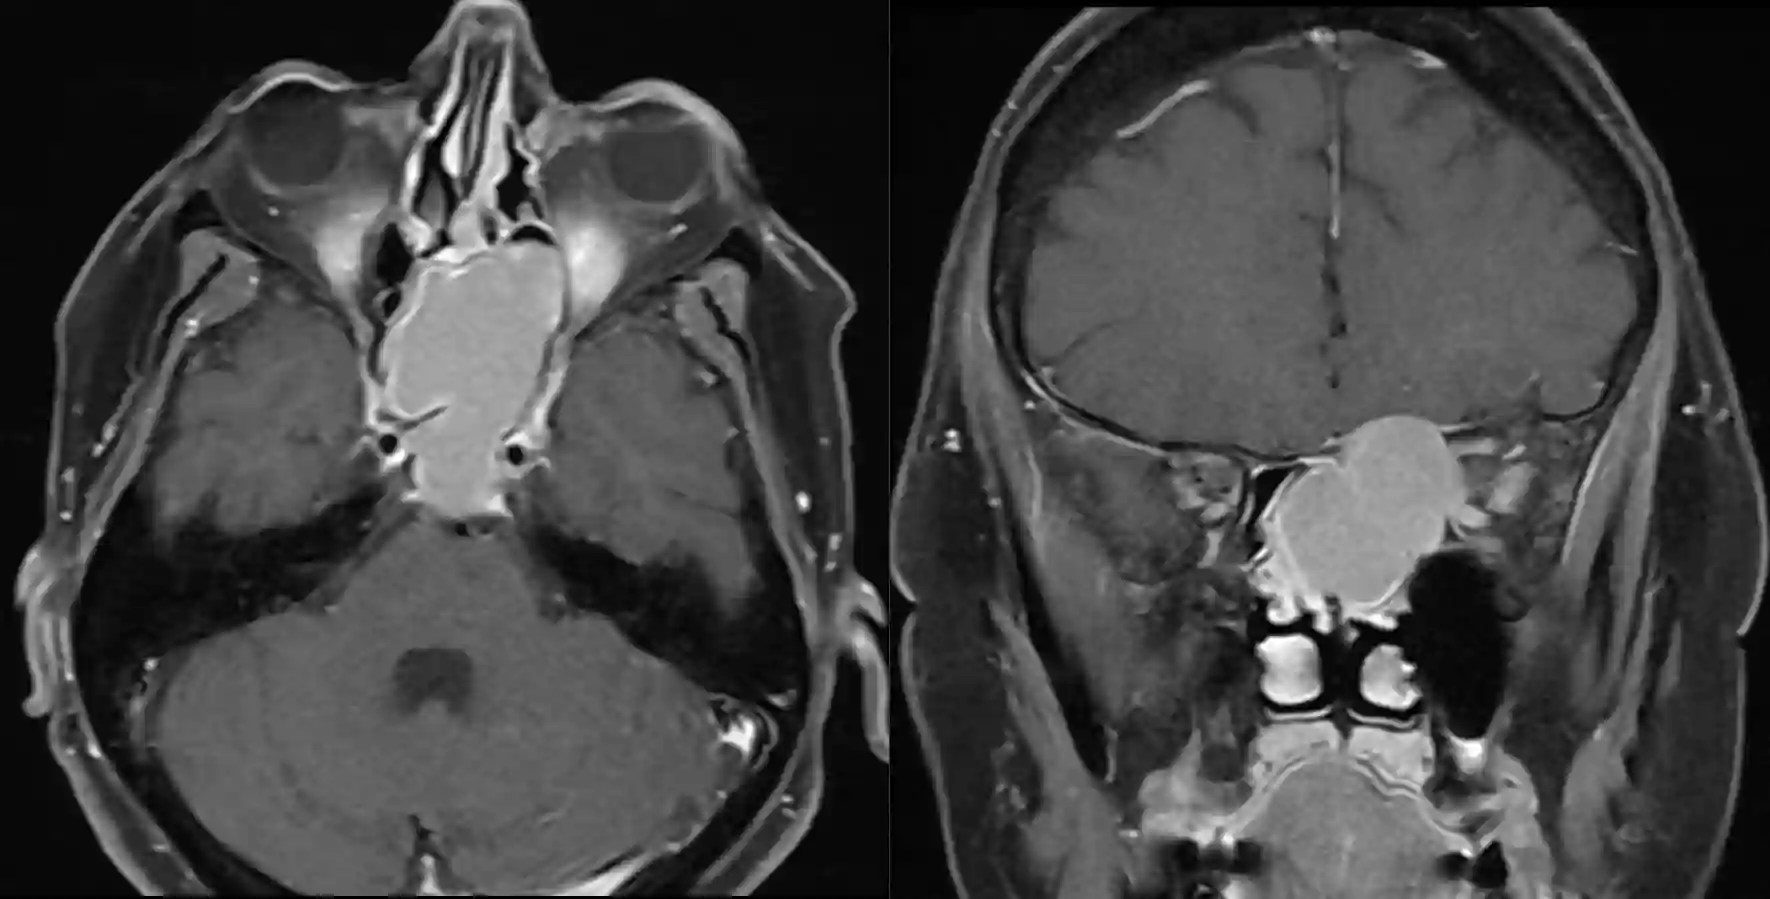

T1 mit Kontrastmittel MRT Bild eines Patienten mit einer Mukozele mehrere Jahre nach einem Schädel-Hirn-Trauma.